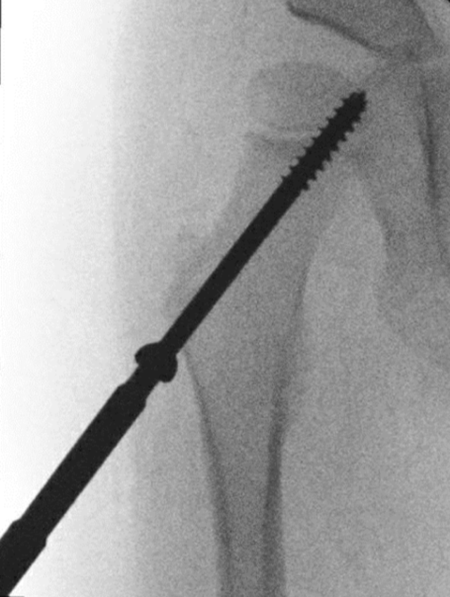

TXA-RCT

Effect of tranexamic acid on intraoperative blood loss in paediatric osteotomies around the hip: a double-